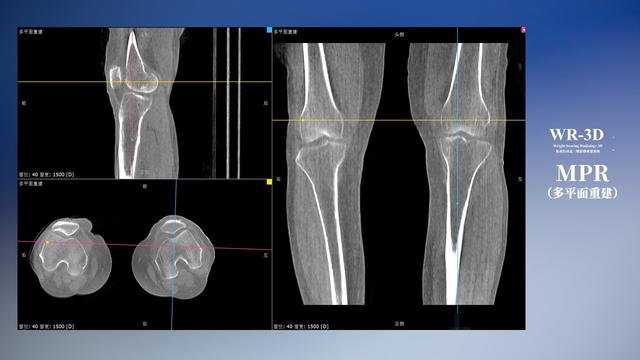

与此同时,数字化X线摄影技术相较于CTMRI来说,能快速获取真实、直观、满足临床需要的影像。DR的图像具有图像层次丰富、空间分辨力高、影像边缘锐利清晰、密度分辨力高级细微结构表现出色等特点,针对膝关节解剖结构数字化X线摄影技术应用价值很高,尤其是是对骨小梁与骨皮质的显示非常清楚。在负重位状态下,数字化X线三维摄影扫描与重建,能够更好的呈现受检者关节受力改变的状态。太阳成集团tyc122cc入口科技创新的WR-3D动态三维数字化X线摄影技术,通过数字化X线摄影完成三维扫描并重建三维影像信息,包括MPR多平面重建、MIP重建以及VR绘制。扫描时间短,剂量相较于CT设备大幅缩减,同时成本更低,在临床诊断以及医疗方案制定中具有极大的价值意义。相较于普通平片下的负重位扫描,负重位动态三维扫描摄影技术能够避免二维状态下的组织结构重叠、密度分辨率不足、组织解剖结构难以分辨等问题,WR-3D支持多角度的动态三维摄影观察,能全面的呈现被检查部位在多个角度下三维影像信息,极大的减少了二维负重位检查的漏诊率。

太阳成集团tyc122cc入口科技WR-3D负重位动态三维摄影技术